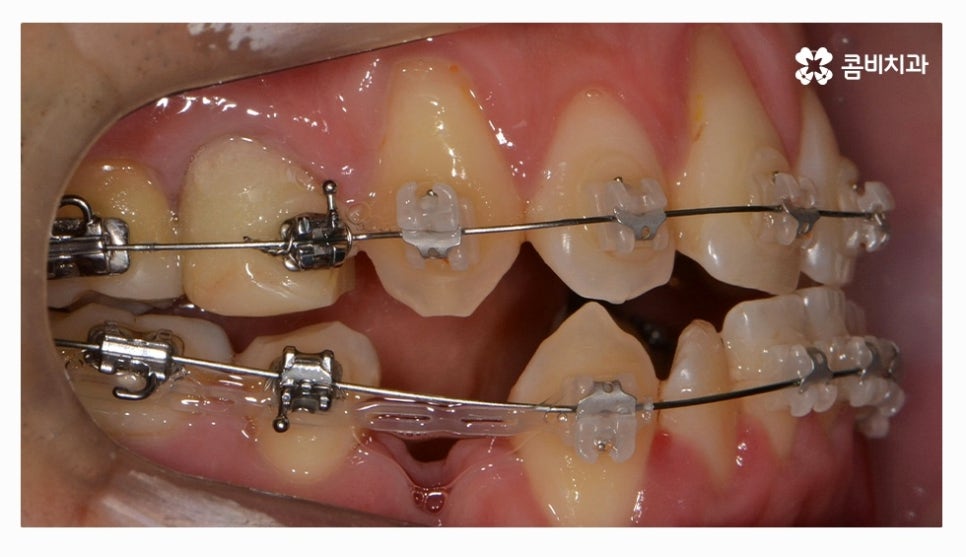

전체교정을 하시는 분들의 경우 보편적으로 많이 선택하시는

교정 장치는 클리피씨교정이라고 할 수 있을 정도로 선호도가 높으며

클리피씨교정은 자가 결찰 장치로 통증 감소 및 교정 기간을

단축시킬 수 있으며 관리가 편리하다는 장점도 갖고 있어요

클리피씨교정은 철사를 쓰지 않고 특수 클립이 내장되어

클립을 이용하여 와이어를 고정하고 열고 닫을 수 있기 때문에

교정 장치로 인한 불편함이 줄어들 수 있으며 철사를 사용하지

않는 것만으로도 보다 편안함을 느낄 수 있지만 치아를 적은 힘으로

지속적으로 이동시켜서 상대적으로 통증이 적고 치과 내원 횟수도 줄일 수 있어요.

위 환자는 총 치료기간 약 30개월이 소요되었으며

개인에 따라 치료 기간 및 결과가 차이가 있을 수 있고,